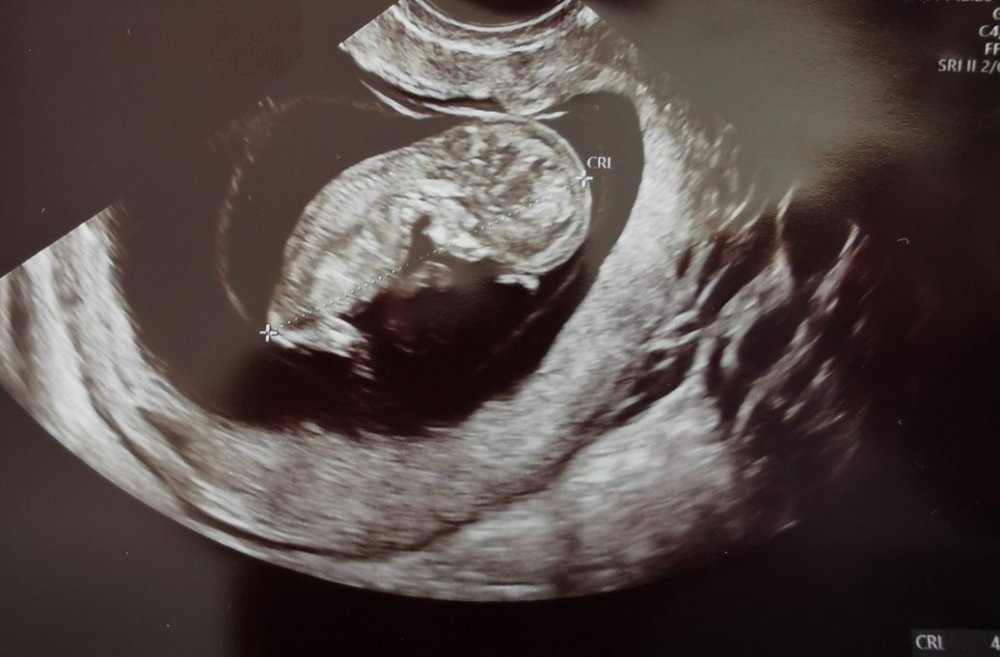

Już po I USG prenatalny.

Wg. USG wszystkie prawidłowo 🥰 jestem mega mega szczęśliwa.

Jeszcze czekam na pobranie krwii do Pappa, ale doktor mówi że to tylko formalność, przy takim obrazie USG

Jaka ja jestem szczęśliwa i już spokojna.

Nie mogę w to uwierzyć!